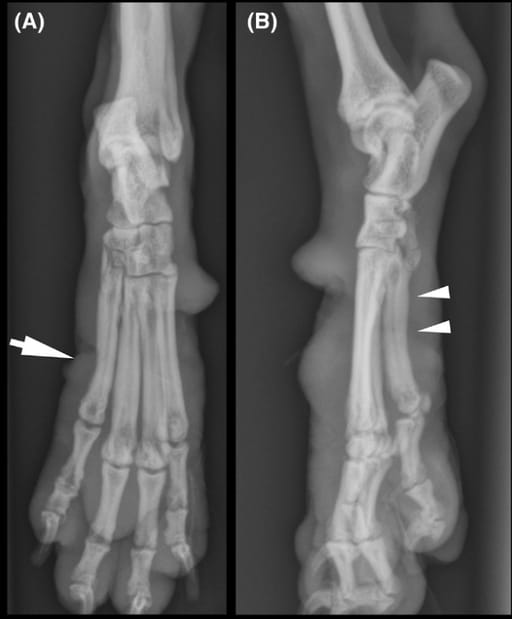

(A) Dorsoplantar and (B) lateral radiographic views of the left pes of a 2-year-old Shih Tzu with strangulating hair matting at the level of the metatarsal bones. A concave defect (arrow) and mild periostitis (arrowheads) are seen on the abaxial surface of the second metatarsal bone at the level of the constriction (2.5 mAs, 86 kVp)

All limbs exhibited soft tissue defects; over half showed osseous lesions. Radiographic findings included bone atrophy, remodeling, focal lysis, and in some cases, subluxation at joints. Complete absence of digits and self-amputation occurred in some cases. Osseous changes were consistently located in distal extremities. There was no correlation between wound appearance and the presence of bone lesions. Histopathology, where available, confirmed ischemic necrosis and granulation with embedded hair shafts, without evidence of foreign materials or osteomyelitis in most cases.